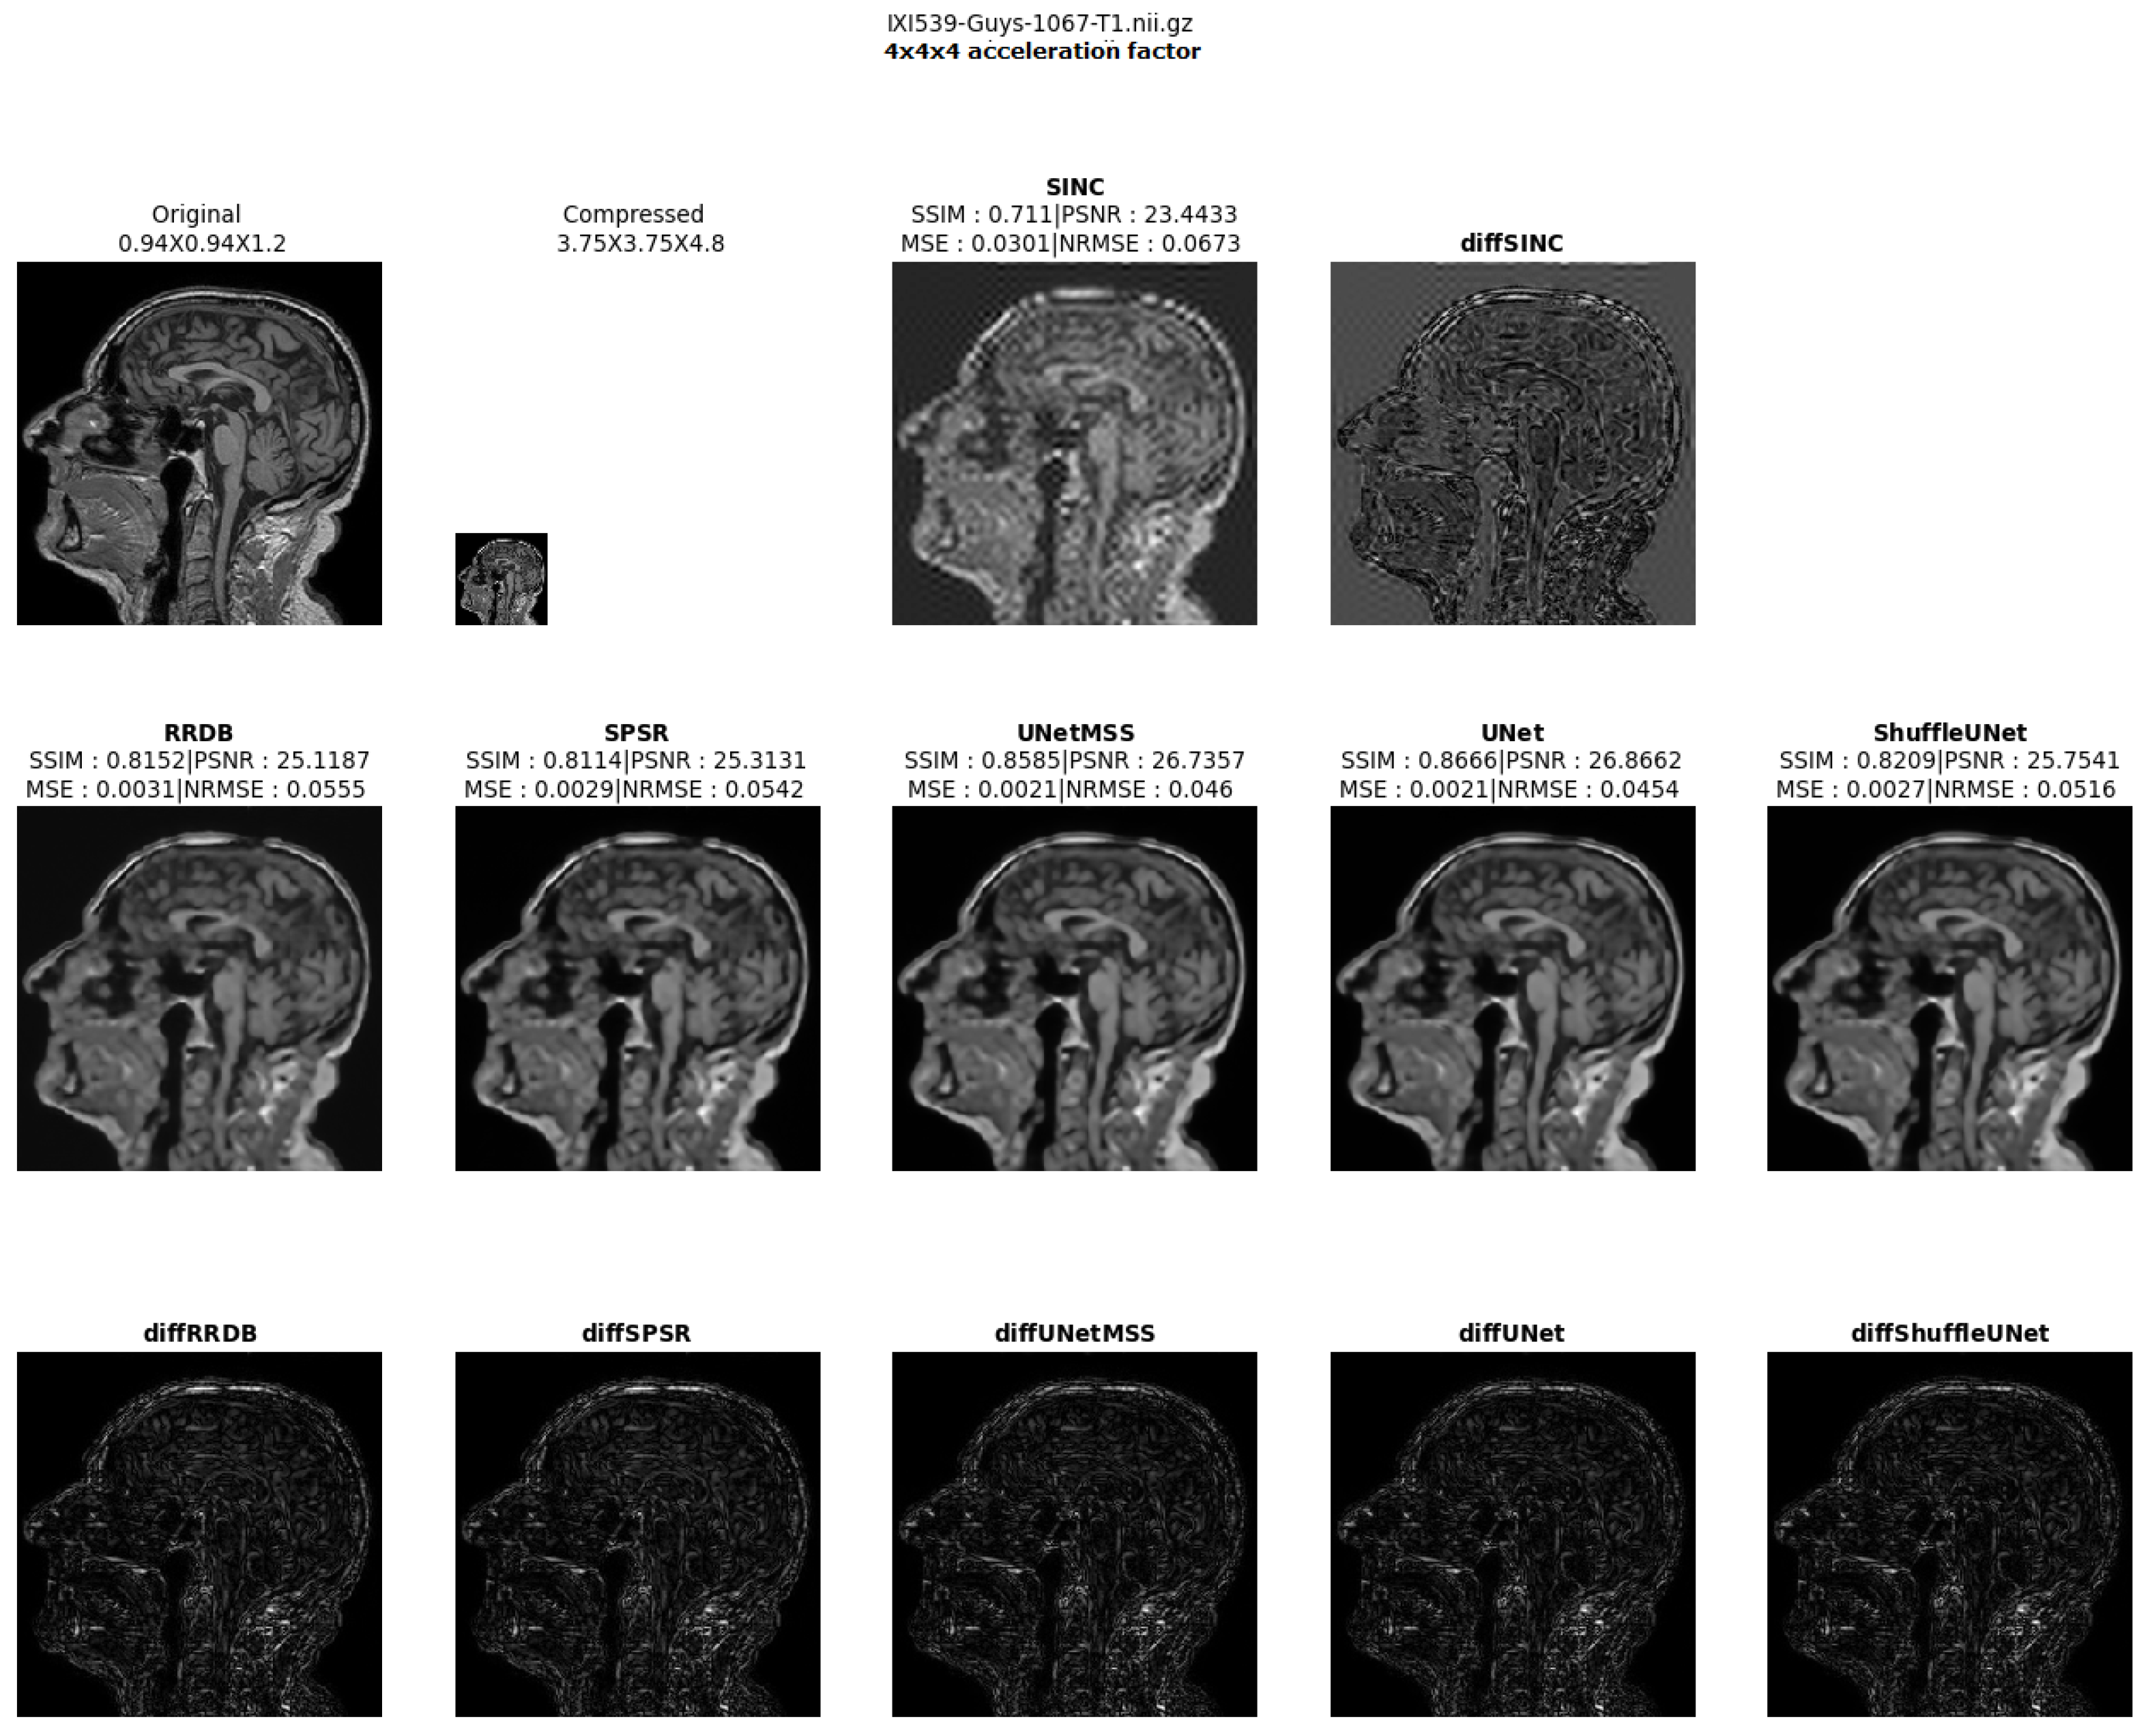

- Visualising individual model results for all the acceleration factors.

Different 3D CNN Models Results Comparison for Cross Acceleration Factor of IXI-T1 Dataset